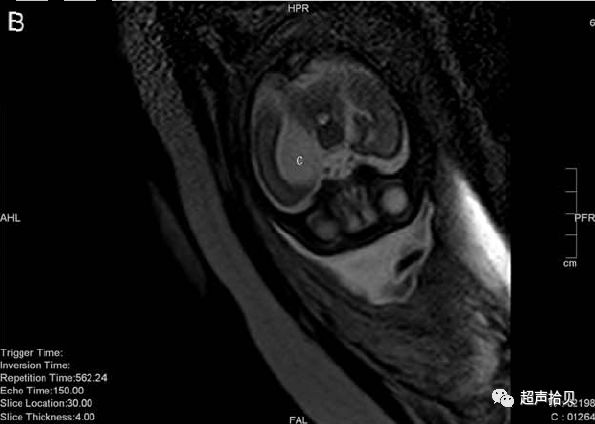

图4:妊娠26周时的产前MRI:第三脑室蛛网膜囊肿的横向(A),矢状(B)和冠状面(C)平面引起脑室扩张